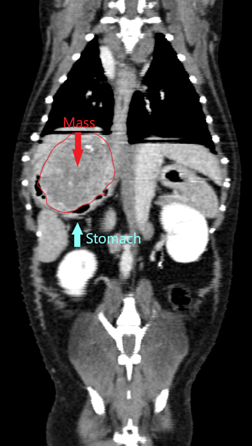

CT thorax/abdomen: Confirmed a partially mineralized gastric mass (approx. 4.1 x 3.8 x 3.2 cm) near the gastroesophageal junction. No metastatic disease observed.